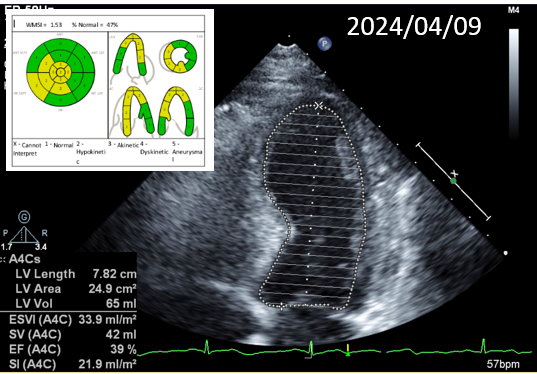

During the staged PCI, antegrade approach with escalating guidewires ended up in subintimal space; retrograde approach from the first LAD-septal branch failed because there was difficulty crossing the existing mid-LAD stent. Further attempts from the third septal branch successfully reached the distal cap of the CTO via proximal descending artery, finally entering the antegrade guide extension catheter by rendezvous technique. After wire externalization and POBA for RCA, the patient became agitated from acute angina, diaphoresis and hypotension. Angiogram of LAD found an acute de novo LAD lesion adjacent to the distal stent edge, leaving only TIMI-1 flow. We stopped the RCA procedure and wired LAD, performed POBA at the de novo LAD lesion and restored coronary blood flow. Then we continued PCI of RCA with POBA followed by the deployment of two DES. Final angiogram showed adequate stent expansion and TIMI-3 flow in RCA. The patient was discharged with no further complications. Follow-up echocardiogram three months later showed improved wall motion and ejection fraction, indicating good myocardial recovery.